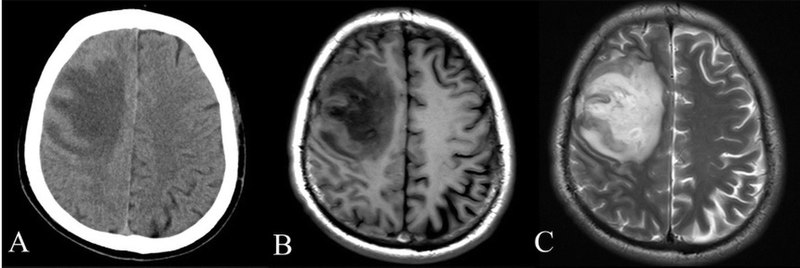

While both CT scans and MRIs have unique benefits, there are significant differences between them. Most notably, a CT scan detects changes and abnormalities in hard tissues. An MRI can provide additional detail about both hard and soft tissues. For this reason, radiologists, oncologists, and other healthcare professionals often order MRI scans when performing cancer screenings and diagnosing diseases.

A CT scan, or computed tomography scan, involves a large X-ray machine. Patients are typically asked to lie down during a CT scan while the X-ray machine takes cross-sectional pictures of the hard tissues inside their bodies. Doctors frequently order CT scans when they suspect that a patient has suffered from a specific type of injury. They’re useful in diagnosing and examining:

An MRI is similar to a CT scan, however, it offers a more detailed look inside the body at various hard and soft tissues. The MRI machine uses magnets and radio waves to give doctors a full image of the tissues and structures inside your body. They’re especially helpful when diagnosing:

Depending on your issues, your doctor may order either a CT scan or an MRI. In many cases, CT scans are ordered first to get a clear immediate picture of the hard tissues in the body, including tumors, etc. Then doctors order an MRI later if they see something on a CT scan that they’re unsure of.

However, MRI and CT scans should be considered complementary rather than the opposite. Many oncologists, radiologists, and medical professionals use both scans to make a complete diagnosis or to develop a more comprehensive treatment plan.